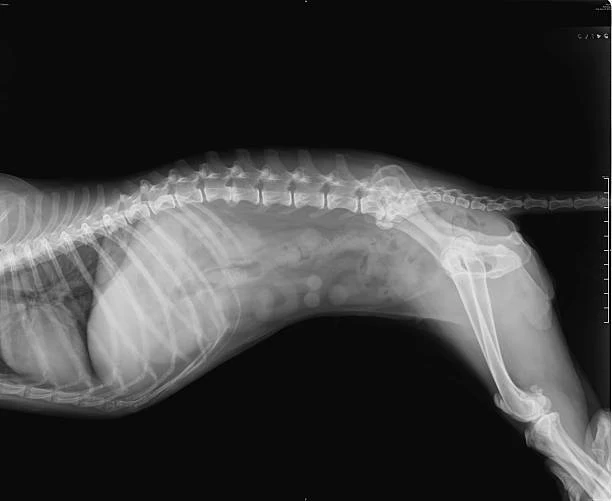

A realização de exames de imagem, como o raio x para animais, é fundamental para auxiliar no diagnóstico e tratamento de diversas condições de saúde que acometem cães, gatos e animais silvestres.

O raio x para animais é um exame indolor e não invasivo, que permite a visualização de ossos, órgãos e tecidos moles do corpo do animal.

Durante o procedimento, o animal é posicionado de maneira adequada para a realização das imagens, que são essenciais para identificar fraturas, tumores, obstruções internas, entre outras condições.